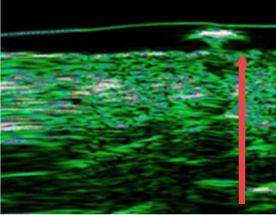

Cải thiện lớp trung bì của da bị mỏng do lão hóa, điều trị thường xuyên và kích thích bên ngoài,

trước thủ thuật

Sau 4 tháng

(độ dày tầng trung bì tăng 12%)

Sau 7 tháng

(độ dày tầng trung bì tăng 27%)